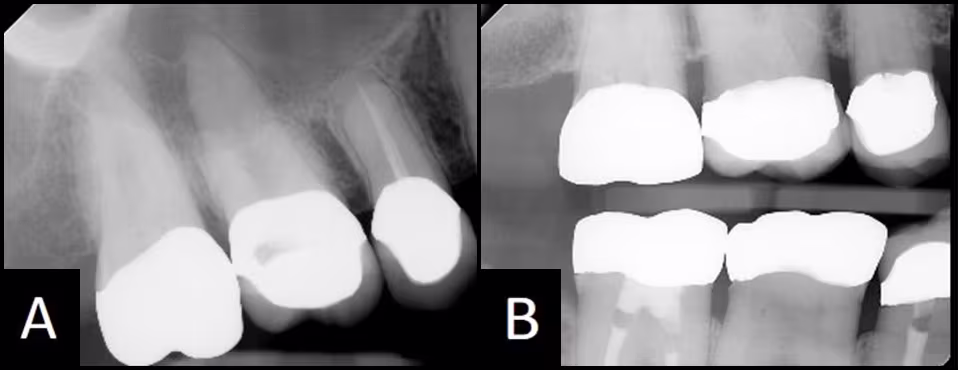

Problem #5: Comparison of periapical images versus bitewing images

Question: Will a periapical of maxillary teeth show caries at the crown margin as well as a bitewing?

Answer and Discussion: NO. The maxillary periapical image is created using +10 to +30 degrees of vertical angulation as compared to a bitewing that is usually created with +5 degrees. The greater vertical angulation changes the way the crown looks on the image. The buccal and lingual margins superimpose part of the root, making diagnosis of the margin impossible. Figure 28 compares a periapical and bitewing of the same crowns. Caries can only be diagnosed from this bitewing image, as the crown margins are covering the root immediately adjacent to the margin on the periapical image.

Figure 28 - Comparison of periapical and bitewing images of the same crowns in the same patient.

(A) The periapical image is not diagnostic for bone levels and crown margins. (B) The crown margins and bone are visible for examination on this ideal Bitewing image.